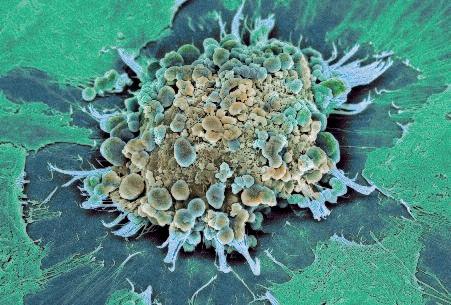

La pagina a fianco mostra l'immagine di una cellula tumorale reale, visualizzata al microscopio elettronico, che ingrandisce questa cellula 6500 volte rispetto alle sue normali dimensioni. Questo tipo di cellula prende il nome di carcinoma, cioè derivante da cellule epiteliali, il tipo di cellule che rivestono sia le superfici interne (polmoni, intestini) che esterne (pelle) del corpo.

Grazie a questo ingrandimento si possono identificare chiaramente alcune delle caratteristiche di tutte le cellule tumorali: a) l'enorme nucleo cellulare dalla forma insolita che spiega la loro grande capacità di riprodursi e b) la struttura non uniforme, complessa della superficie cellulare, che riflette una forte attività di secrezione di sostanze prodotte dalle cellule tumorali.

Una delle più importanti molecole secrete dalle cellule tumorali in grandi quantità sono gli enzimi a ‘forbice’ che digeriscono il collagene. Sono aggiunti graficamente a questa immagine, sotto forma di strutture simili ad un ‘pacman’ rosso.

Naturalmente questi sfere, nella vita reale, sono molecole biologiche, proteine, che hanno la capacità di tagliare le fibre di collagene e di altre molecole del tessuto connettivo. L‘immagine sopra mostra che non c’è un solo tipo di 'pacman' ovvero di queste molecole, ma

Digestione del tessut o connet tivo del tessuto connetti vo diversi tipi, quali il plasminogeno/plasmina e le metalloproteasi (strutture colorate tridimensionali). Queste molecole migliorano il loro effetto distruttivo attivandosi reciprocamente in forma di reazione a catena in cascata.